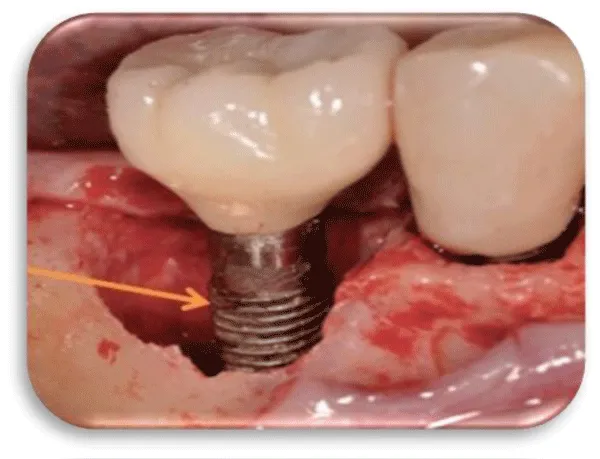

With the progression of the peri-implant mucositis, the soft tissue condition around the dental implant is aggravated. Bone tissue destruction begins inside the alveolar bone around the implant itself, causing bone resorption. This process is irreversible in relation to peri-implant mucositis that is a reversible process (Figures 5-7) [17].

An early stage of peri-implantitis is when the clinical examination in the patient, in the course of the probing, the depth of the gingival sulcus is. In the case of probing, there is a cranny and sometimes drainage of purulent contents. Marginal bone resorption is <25% of the length of the dental implant.

A moderate stage of peri-implantitis exists when, when probe around the dental implant, the probe in the gingival sulcus collapses and drainage of bloody or purulent content occurs. Bone tissue resorption is from 25% to 50% of the length of the dental implant.

Late stage of peri-implantitis, we have when when probe around the dental implant, the probe falls into the sulcus in depth. Bleeding and purulent content drainage is being drained. Bone resorption is> 50% of the length of the dental implant (Figures 8-10) [18].

The first patient was at the age of 48 with male gender and generally with good health. There are no contraindications to make oral surgery. The patient is not allergic to any medication. A dental implant was placed 12 months ago (Figures 11,12), the dental implant’s position was 46. The implant was 4.1 mm in diameter and 12 mm in length. The patient has peri-implantitis, a RTG intraoral radiography image was recorded and marginal bone resorption was observed. The depth of the gingival sulcus was 10mm. Dehiscencia was seen in the patient from the buccal side of the implant (Figure 13). The bone defect was closed with a bone graft (Figures 14-16).